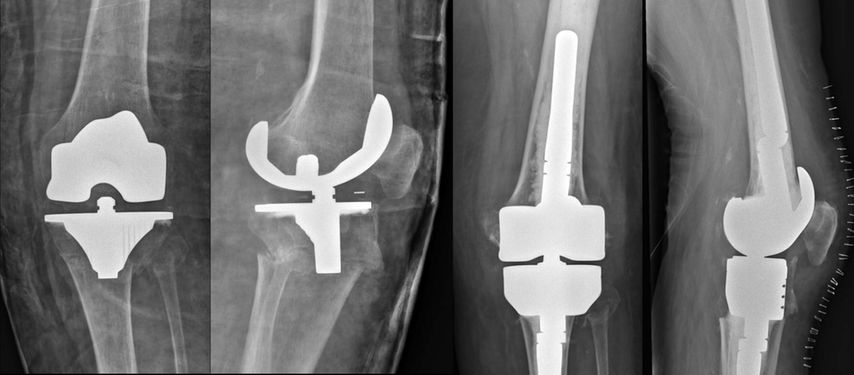

Abb. 1: Periprothetische Tibiafraktur vom Typ II nach Felix et al. (Mayo-Klassifikation). Die Autoren versorgten diese Fraktur mittels proximalen Tibiaersatzes sowie armierter Patellarsehne und führten einen kompletten Systemwechsel durch

Abb. 2: Periprothetische Femurfraktur vom Typ III nach Su et al. Die Autoren versorgten diese Fraktur mittels distalen Femurersatzes und kompletten Systemwechsels